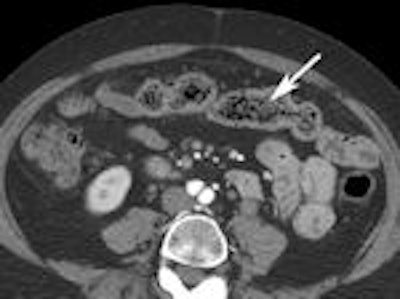

A 2007 study by University of Michigan gastroenterologist Dr. Peter D.R. Higgins showcases the diagnostic power of CT enterography (CTE) for evaluating small bowel Crohn's disease.

Higgins concluded that CTE offered complementary information about symptoms of obstruction in Crohn's disease (Inflammatory Bowel Diseases, March 2007; Vol. 14:3, pp. 262-268).

The following images from Higgins' study illustrate some of the clinically relevant findings about Crohn's disease that can be made with CTE.

Left: Mesenteric stranding. Right: Extraluminal gas.